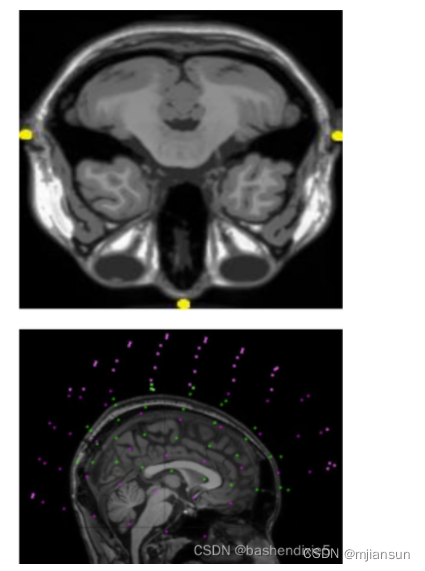

在医学领域,多模式 MRI-MEG 联合配准。在大脑成像的轴向视图中,顶部的黄点表示解剖标记或基准点(解剖信息)。底部:粉红色的点表示 MEG 传感器的位置,而绿点表示头皮脑电图传感器的位置。功能信息包含在这些 MEG 和 EEG 数据中,底部图像描绘了共同配准的大脑图像。